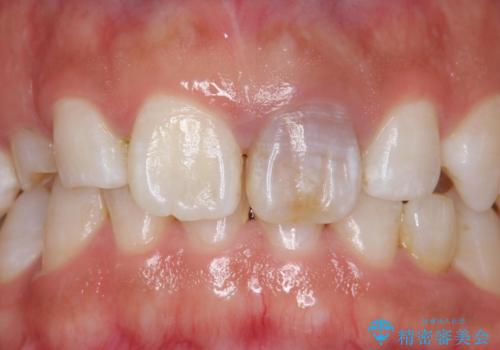

モザイク模様の前歯 オールセラミッククラウンで整った印象に